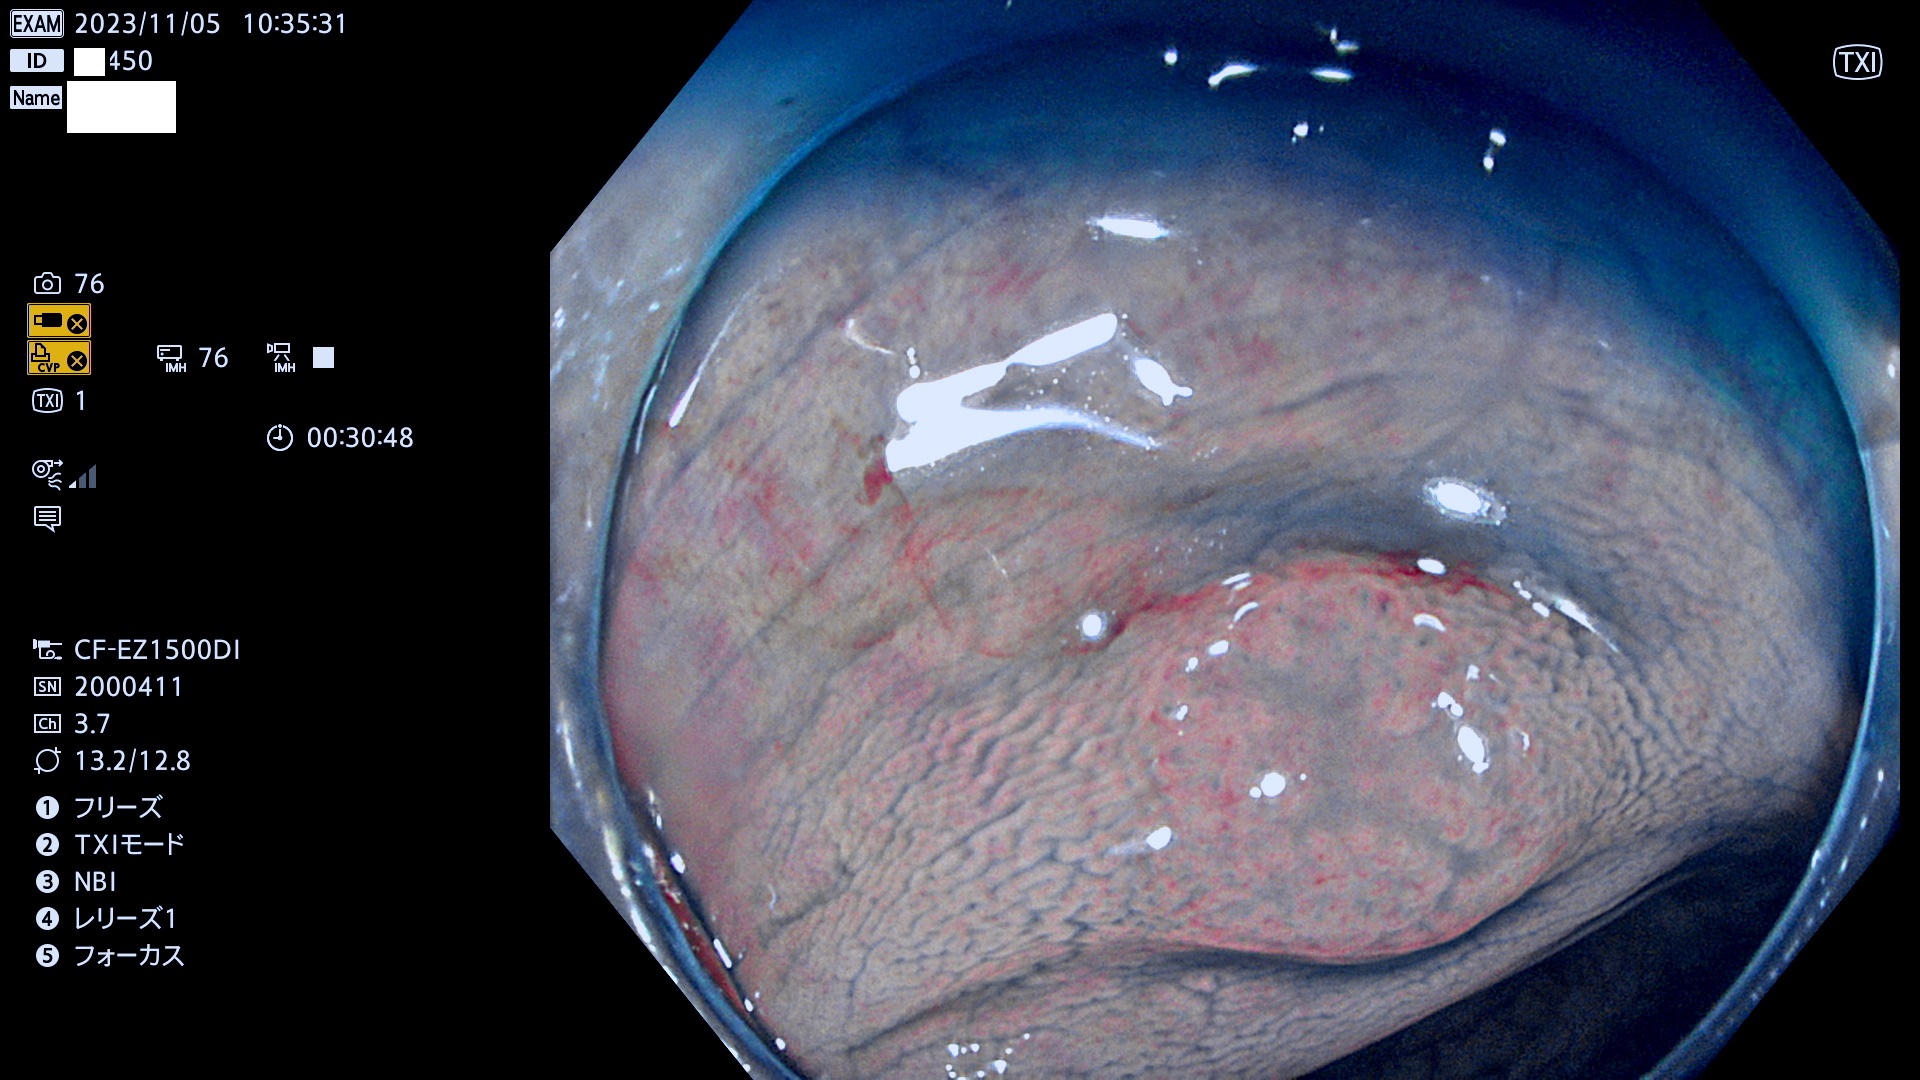

今週のUb、Uc型腺腫

表面型腺腫(Flat Adenoma)の中で、完全に平坦な物をUb、陥凹している物をUcと呼びます。平坦隆起型(Ua)よりも、発見が難しく危険な病変です。このタイプは「内視鏡後・大腸癌の重要犯人」であり、この発見率は「腺腫発見率」よりも、重要な意味があります。

毎週の検査(木・金・土・日)に発見されたUb、Uc型・腺腫を、その週の日曜の夜にUPし1週間、提示します。

抽出の対象期間 2023年11月2日(木)〜11月6(月)の5日間(60件の検査)11件